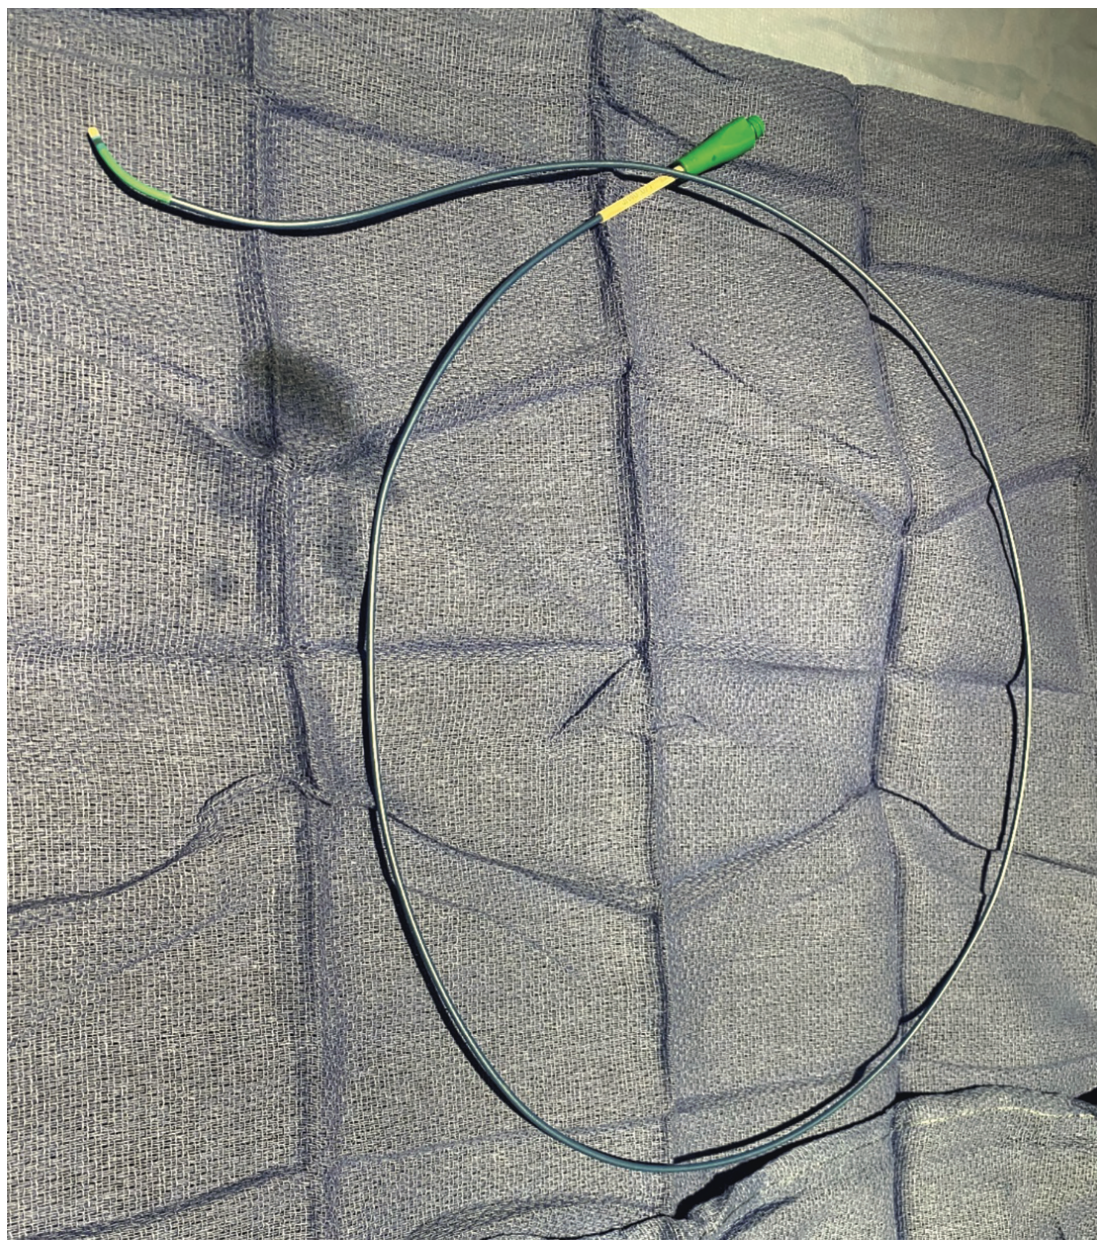

Femoral access was gained with a 6.0 Fr, 24 cm Arrow-Flex sheath (Telflex) (note longer sheaths can be used if desired). After routine coronary angiography, the aortic valve was crossed with a 5 Fr Judkin right 4.0 (JR4) catheter over a standard .014-inch J wire. Alternatively, to save a step, Amplatz left guiding catheters and moveable or fixed core straight wires can be directly placed in the LV. Simultaneous LV and aortic pressures were measured using the femoral long sheath pressure as a surrogate for the ascending aortic pressure, after verifying that aortic root and long sheath pressures were identical and superimposable, which is another technique useful for quickly measuring LV-aortic gradients. The use of this gradient as a surrogate for aortic root-to-LV gradients has been controversial; however, we find it to be suitable for most routine clinical decision making. Subsequently, the 5 Fr JR4 catheter was exchanged for a 6 Fr JR4 guide catheter over a standard .035-inch exchange-length J wire and the aortic valve was crossed with a JR4 guide catheter. An .014-inch Runthrough coronary wire (Terumo) was advanced into the LV. The guide catheter was pulled back into the ascending aorta, leaving the Runthrough in the LV. Next, a Twin-Pass microcatheter was advanced into the LV over the Runthrough wire. Simultaneous LV and aortic pressures were measured using the Twin-Pass and guide catheter. During pullback, premature ventricular contractions (PVCs) were induced when necessary with the Runthrough wire, and resting and provoked gradients were measured precisely, easily, and repetitively at various locations within the LV using LV-aortic pullbacks of the Twin-Pass over the guidewire. The pressure gradient, when measured by using the femoral sheath as a surrogate for the ascending aortic pressure and by directly measuring the ascending aortic pressure with the JR4 catheter, correlated well between the two techniques. The absence of a transvalvular pressure gradient and the presence of a LV outflow gradient with Brockenbrough-Braunwald-Morrow sign were evident, and these dynamic obstructive hemodynamics were easily measured and demonstrated with guidewire-provoked PVCs. Once measurements were complete, all catheters and wires were removed. Hemostasis was achieved with the use of an Angio-Seal (Terumo). Figures 1-5 show the instruments that were used and the waveforms that were obtained in this case.

The use of the Twin-Pass catheter within a standard guiding catheter is helpful for the simultaneous measurements of aortic and LV pressures and LV outlow tract gradient measurements. In our experience, this technique also correlates well with the use of the femoral arterial sheath as a surrogate for the ascending aortic pressure. In the era of the Langston catheter recall, this technique may be used for the measurement of aortic stenosis and left ventricular outflow tract obstruction. An .014-inch Runthrough wire can induce PVCs to elicit the Brockenbrough-Braunwald-Morrow sign and further differentiate valvular aortic stenosis from hypertrophic obstructive cardiomyopathy.

Various methods to simultaneously measure aortic and left ventricular pressures have been described. The use of a Twin-Pass catheter with a 6 Fr coronary guiding catheter over an .014-inch coronary wire is a feasible, accurate, and elegant approach, allowing for precisely positioned, invasive evaluation of aortic valve stenosis and left ventricular outflow pressure gradients, as well as intracavitary obstructive gradients.